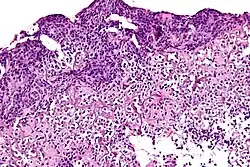

![]() |

Tuberculous lymphadenitis | Caseating granulomatous lesion with areas of amorphous granular eosinophilic necrotic debris known as caseation (on the right half) bordered by collections of epitheloid cells, Langhan giant cells and lymphocytes. | Category: Histopathology of tuberculous lymphadenitis | Tuberculous lymphadentis |